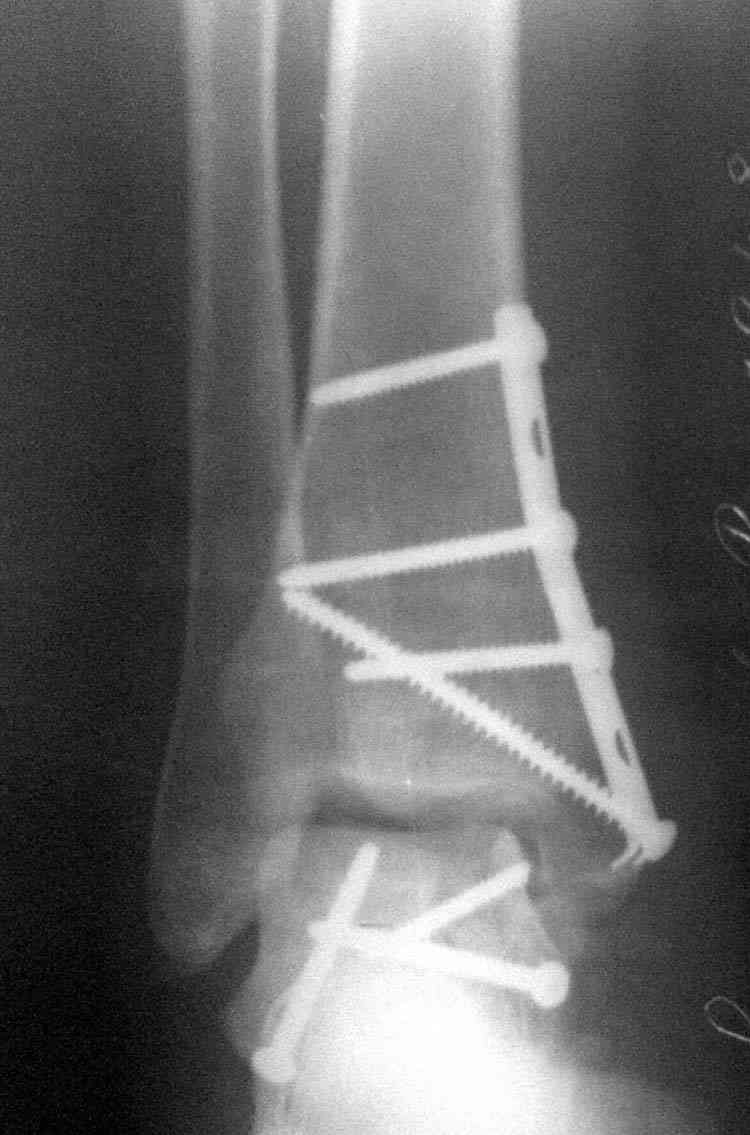

Случай с множественным оскольчатым переломом тарана оперированный из двойного доступа.

Через 2 мес.: